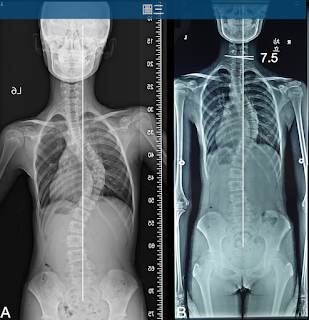

圖二 經過三個月的大腦學習訓練法,胸椎側彎由60度降為50度、腰椎側彎由37度變為35度

接受大腦學習訓練法3個月,胸椎側彎主彎由60度降到50度、腰椎彎度由37度變為35度(圖二)。該個案試圖將頸椎帶往骨盆正上方時,因施力方向錯誤,導致頸椎第七節傾斜了7.5度(圖三)。

圖三 進行側彎矯正時,雖然將頭頸、中段胸椎及腰椎都帶往中心線(B),但該個案的頭頸部力量控制方向錯誤,導致頸椎第七節傾斜7.5度